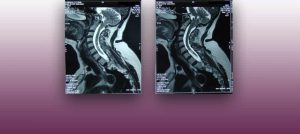

Institut Chiari & Siringomielia & Escoliosis de Barcelona is highly specialized neurosurgical center dedicated to the diagnosis and treatment of spinal and brain disorders, with a focus on the clinical concept of Filum Terminale Disease. Conditions treated include: